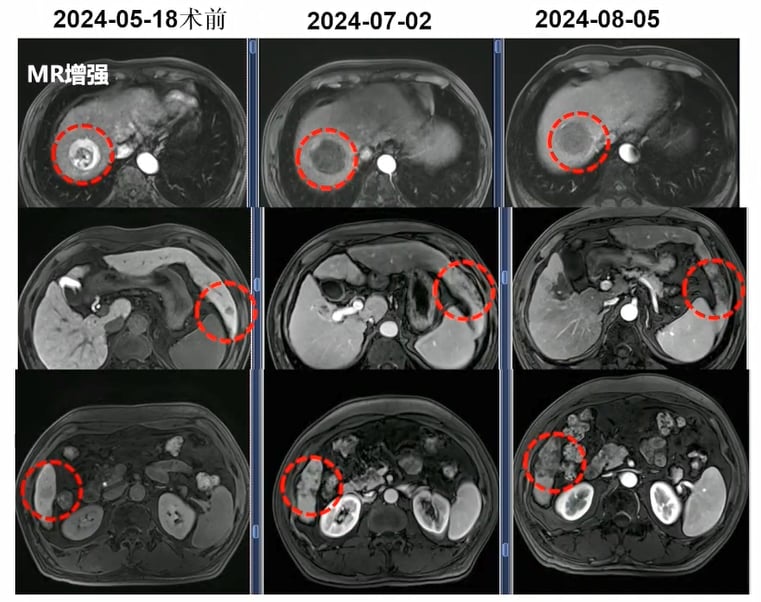

部分肝细胞癌患者在钇90后可见明显影像学缓解。

部分病例中,钇90不仅缩瘤,还可能为后续转化治疗争取机会。